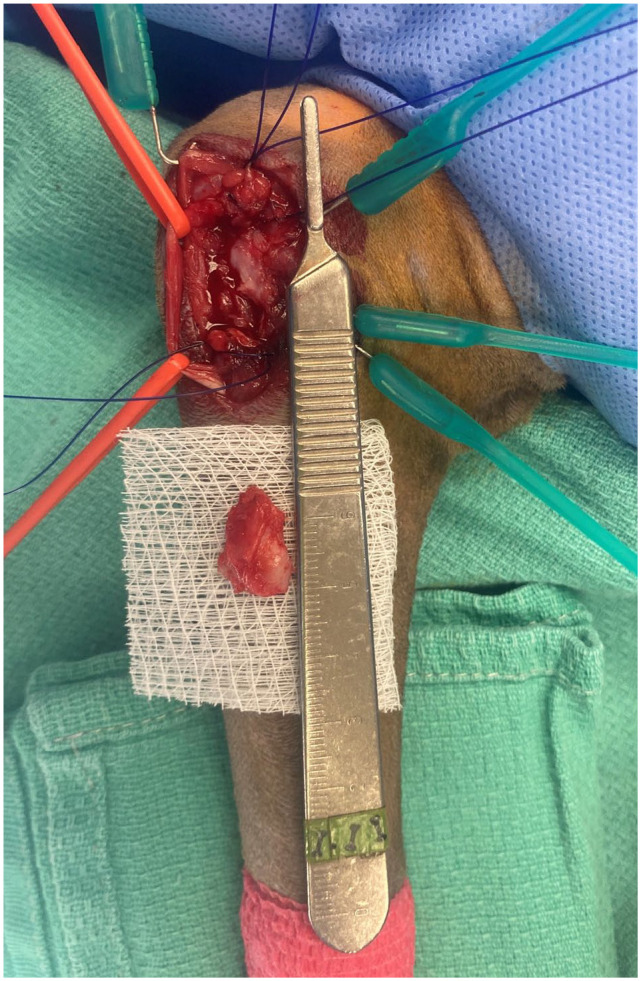

本研究的目的是描述患有内侧肱骨上髁炎(MHE)的猫的临床表现、诊断结果和非手术和手术治疗的反应。我们检索了一家机构的医疗记录,寻找经放射学证实诊断为MHE的猫,这些猫单独进行非手术治疗或同时进行非手术和手术治疗。包括9只猫(17只肘部)。这些猫都没有户外活动的记录。骨科检查显示触诊内侧上髁疼痛(n = 15),肘关节旋前(n = 7)或腕屈曲(n = 7),内侧上髁远端可触及矿化(n = 7)。上髁炎放射学分级为轻度(n = 8)、中度(n = 7)和重度(n = 2)。在10个肘部进行了CT检查,在7个肘部发现了额外的信息,包括5个肘部的关节内矿化体。在四个肘部进行超声检查,发现尺侧腕屈肌周围有液体。非手术治疗后,4只猫无反应,4只猫部分反应,1只猫完全反应。放射学变化不那么严重的猫似乎表现出更有利的反应。4只猫(7只肘部)接受了手术治疗,所有猫都有明显的尺神经炎。3只猫(5只肘部)术后跛行消失。隐伏的中度跛行与触诊疼痛相关的内上髁尾远端疼痛应该增加MHE的怀疑指数,并及时评估是否存在可触及的矿化和腕屈疼痛。尺神经炎是常见的猫与MHE,他们经常出现游离关节矿化体。x线摄影只能检测晚期或慢性MHE,此时非手术治疗可能无效。早期超声诊断可改善非手术治疗后的预后。

Case series summary The aim of this study was to describe the clinical findings, diagnostic results and response to both non-surgical and surgical therapy in cats with medial humeral epicondylitis (MHE). The medical records of one institution were searched for cats with a radiographically confirmed diagnosis of MHE where non-surgical therapy alone or both non-surgical and surgical therapy had been trialed. Nine cats (17 elbows) were included. None of the cats had a history of outdoor access. Orthopedic examination revealed pain upon palpation over the medial epicondyle (n = 15), elbow pronation/supination (n = 7) or carpal flexion (n = 7) and palpable mineralization distal to the medial epicondyle (n = 7). Epicondylitis was radiographically graded as mild (n = 8), moderate (n = 7) or severe (n = 2). CT was performed in 10 elbows and revealed additional information in seven, including intra-articular mineralized bodies in five elbows. Ultrasound was performed in four elbows and revealed fluid surrounding the flexor carpi ulnaris muscle. After non-surgical management, four cats showed no response, four showed a partial response and one showed a complete response. Cats with less advanced radiographic changes appeared to show more favorable responses. Four cats (seven elbows) underwent surgical treatment with ulnar neuritis being evident in all. Lameness resolved postoperatively in three cats (five elbows).Relevance and novel information An insidious onset of moderate-grade lameness associated with pain on palpation caudodistal to the medial epicondyle should increase the index of suspicion for MHE and prompt assessment for the presence of palpable mineralization and pain on carpal flexion. Ulnar neuritis is common in cats with MHE and they frequently present with free articular mineralized bodies. Radiographs can only detect advanced or chronic stages of MHE, by which time non-surgical management is likely to be ineffective. Earlier diagnosis using ultrasound may improve the prognosis after non-surgical management.